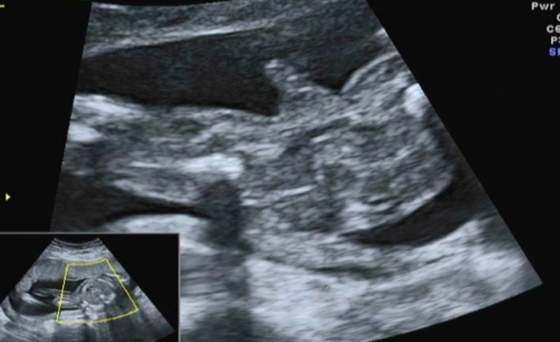

U mnie jest różnica, bo za normalne USG, które mam na wizycie w gina płacę 100złŚliczne dzieciaczki Sivle i Baśka ... wielkie gratki :-)

Zgadzam sie z Wami ,ze takie badanie prenatalne w trybie 3D/4D to niemały wydatek. U mnie kosztuje to 170zł, ale normalna wizyta kosztuje 100zł , więc czy az taka różnica?!